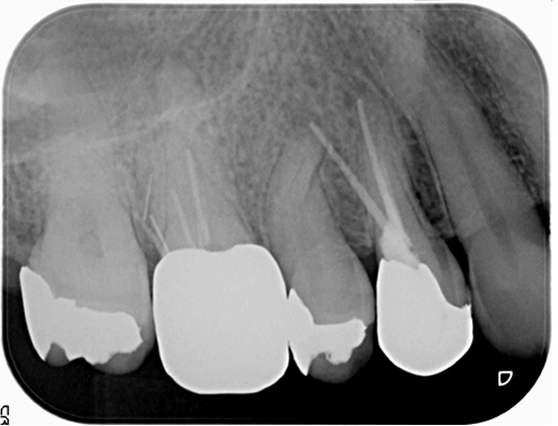

右上4番(右から2番目の歯)を再治療したが治らないとのことで来院。診査したところ、原因は右上5番(右から3番目)の歯の神経が死んでしまっていたためでした。右上5番は通常通り根管治療を行いました。

同時に右上6番に違和感を感じているとのことでしたが、右上6番には歯の横に穴があいており、破折器具が残っている状態でした。破折器具を除去し、根管治療を行いました。(骨内に残った器具は感染源となっておらず、症状が完全に消失したため外科を避けて経過観察としました。その後1年半の経過観察で良好な経過を送っています。